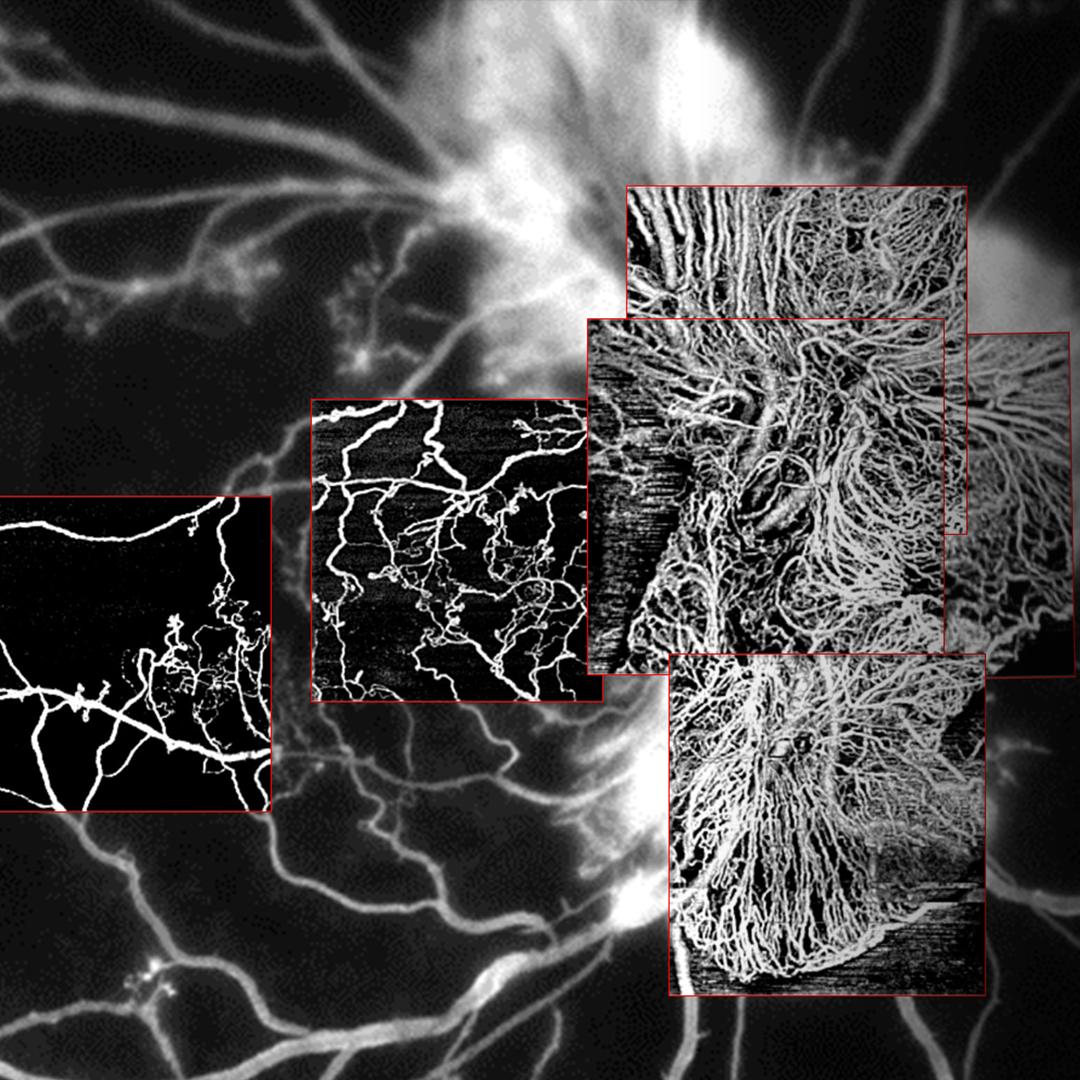

• Reveal the finer details of the retinal microvasculature

Reveal the finer details of the retinal microvasculature

Revele os detalhes mais sutis da micro vasculatura retiniana

Com apenas um clique, isole as camadas retinianas de interesse, desde a interface vítreo-retiniana até as regiões mais profundas da coroide.

• 3x3 mm AngioPlex OCTA of proliferative diabetic retinopathy (PDR)

3x3 mm AngioPlex OCTA of proliferative diabetic retinopathy (PDR).

Image courtesy of Roger Goldberg, MD, Bay Area Retina Associates